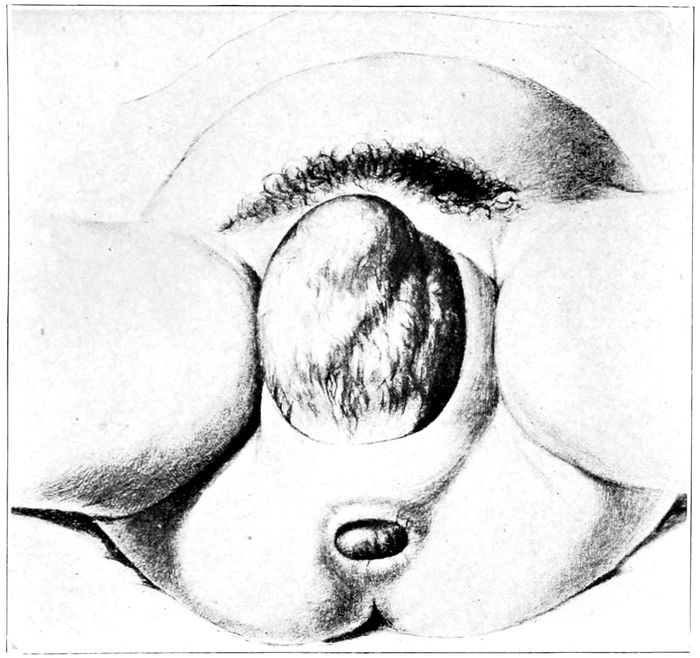

| 42. |

The head passing over the perineum |

117 |

| |